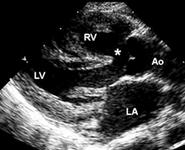

Imagen de ecocardiografía de 4 cámaras apical de una comunicación auriculoventricular (CAV) completa. Observe la comunicación interauricular (CIA) de tipo ostium primum (*) y la comunicación interventricular (CIV) de entrada contigua (flecha). (AD) aurícula derecha; (AI) aurícula izquierda; (VD) ventrículo derecho; (VI) ventrículo izquierdo